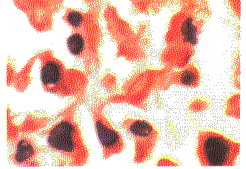

心包內惡性畸胎瘤畸胎瘤的病理特徵為腫瘤組織由外、中、內三個胚層組織構成,常含有成熟或未成熟的皮膚、牙齒、骨、軟骨、神經、肌肉、脂肪、上皮等組織,少數亦可含有胃黏膜、胰、肝、腎、肺、甲狀腺及胸腺等組織成分。惡性畸胎瘤常表現為未成熟的不易定型和分辨的組織,畸胎瘤的惡變多表現為神經組織或上皮組織的異常增殖而形成惡性畸胎瘤。

畸胎瘤的病理分類為:①成熟型畸胎瘤:即良性畸胎瘤,由已分化成熟的組織構成;②未成熟型畸胎瘤:即惡性畸胎瘤,由胚胎髮生期的未成熟組織結構構成,多為神經膠質或神經管樣結構,常有未分化、有絲分裂增多的惡性病理表現。過去有將精原細胞瘤、無性細胞瘤、胚胎癌、內胚竇瘤等生殖細胞惡性腫瘤統稱為惡性畸胎瘤,事實上它們是胚胎學上生殖細胞瘤、自卵黃囊向生殖腺移行的各個區域中發生異常分化的結果,在病理上常無三胚層結構,不應歸為畸胎瘤。